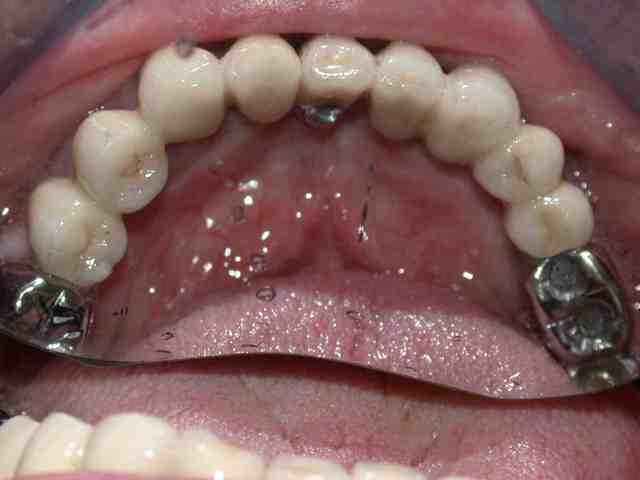

je continue donc :

comme vous l'aviez vu 12 était le siège d'une provisoire (comme par hasard en place depuis le début) donc cette dent ne peut être conservé dans des conditions favorables (snif pour elle) : exo

dépose des anciennes couronnes réalisation d'un bridge provisoire : la je peux vous dire que le patient est plus qu'heureux

pose de trois implants en 24 25 26 attente de l'ostéointégration au maxllaire et je poursuis sur la prothèse mandibulaire

avulsion de la 34 (vous me suivez toujours) mise en fonction des 4 de devant

bridge transvissé sur 37 36 35 scellé sur fm implantaire sur 32 31 .

couronnes unitaires sur 42 41 (41 mal située position un peu trop lingual : la vue linguale de la photo montre notre solution prothétique pour l'axe)

bridge dentoporté sur 47 46 44 43

pano et photos a suivre les photos sont pas tops car vieil apparei et je vous le rappelle (reflex nauseeux,faut pas aller chercher trop loin quand même , mais vous verrez à la fin on met des écarteurs photos si si...)